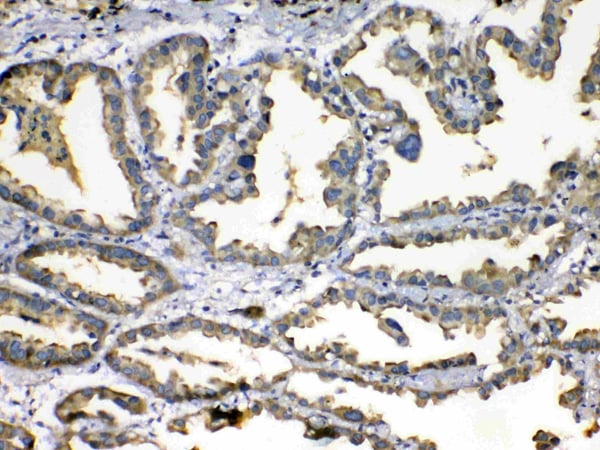

(Figure 1. IHC analysis of SOD3 using anti-SOD3 antibody (AAA124668).SOD3 was detected in paraffin-embedded section of human lung cancer tissue. Heat mediated antigen retrieval was performed in citrate buffer (pH6, epitope retrieval solution) for 20 mins. The tissue section was blocked with 10% goat serum. The tissue section was then incubated with 1ug/ml rabbit anti-SOD3 Antibody (AAA124668) overnight at 4 degree C. Biotinylated goat anti-rabbit IgG was used as secondary antibody and incubated for 30 minutes at 37 degree C. The tissue section was developed using Strepavidin-Biotin-Complex (SABC) with DAB as the chromogen.)